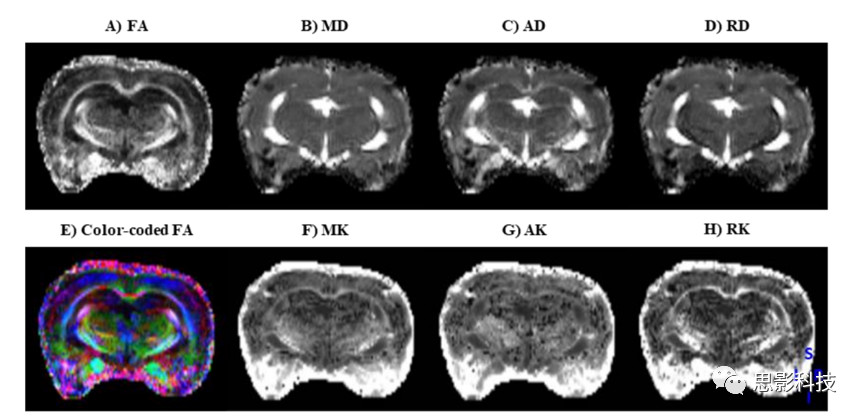

思影根據(jù)不同的數(shù)據(jù)類型以及客戶的不同需求,可構(gòu)建多種彌散模型(如彌散張量DTI、彌散峰度成像DKI、神經(jīng)突強(qiáng)度和散度成像NODDI等等)并計(jì)算對(duì)應(yīng)的彌散指標(biāo)。

DTIDKI指標(biāo)圖圖例